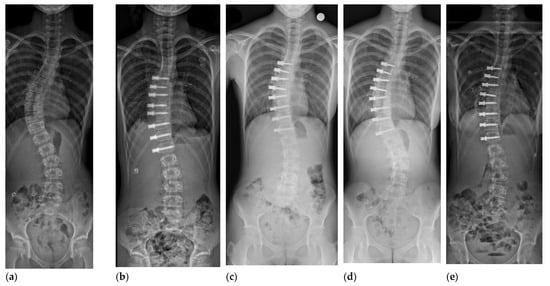

3. Anterior Vertebral Body Tethering

3.3. Technical Considerations for Vertebral Body Tethering

4.1. Curve Correction after AVBT in Thoracic Curves